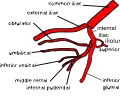

Internal iliac artery

The internal iliac artery (formerly known as the hypogastric artery) is the main artery of the pelvis.

The internal iliac artery supplies the walls and viscera of the pelvis, the buttock, the reproductive organs, and the medial compartment of the thigh. The vesicular branches of the internal iliac arteries supply the bladder.[1]

It is a short, thick vessel, smaller than the external iliac artery, and about 3 to 4 cm in length.

Hypogastric vessels